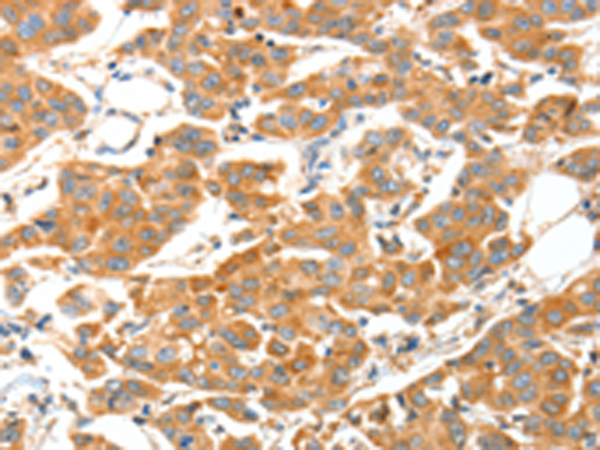

分类: 科研抗体货号: P07796别名:应用: IHC反应种属: Human